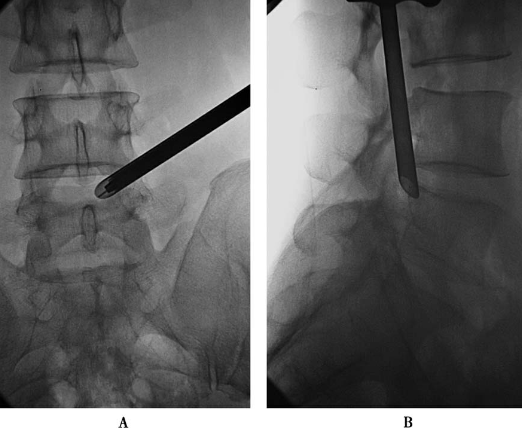

置入1级导杆:使头端到达第一靶点(图15)。

图15 置入1级导杆A.前后位透视头端到达第一靶点;B.侧位透视头端抵达L5椎体后上缘。

依次置入1~3级扩张管扩张软组织通道,3级扩张管在椎间孔外受阻(图16)。

图16 依次置入1级~3级扩张管,扩张软组织通道,3级扩张管在椎间孔外受阻。

第一靶点成形:在导丝、1级导杆、1级扩张管与3级扩张管间,逆时针旋入1级环锯,进行1级扩孔环锯头端扺达第一靶点(图17)。

图17 第一靶点成形:前后位透视环锯头端抵达第一靶点。